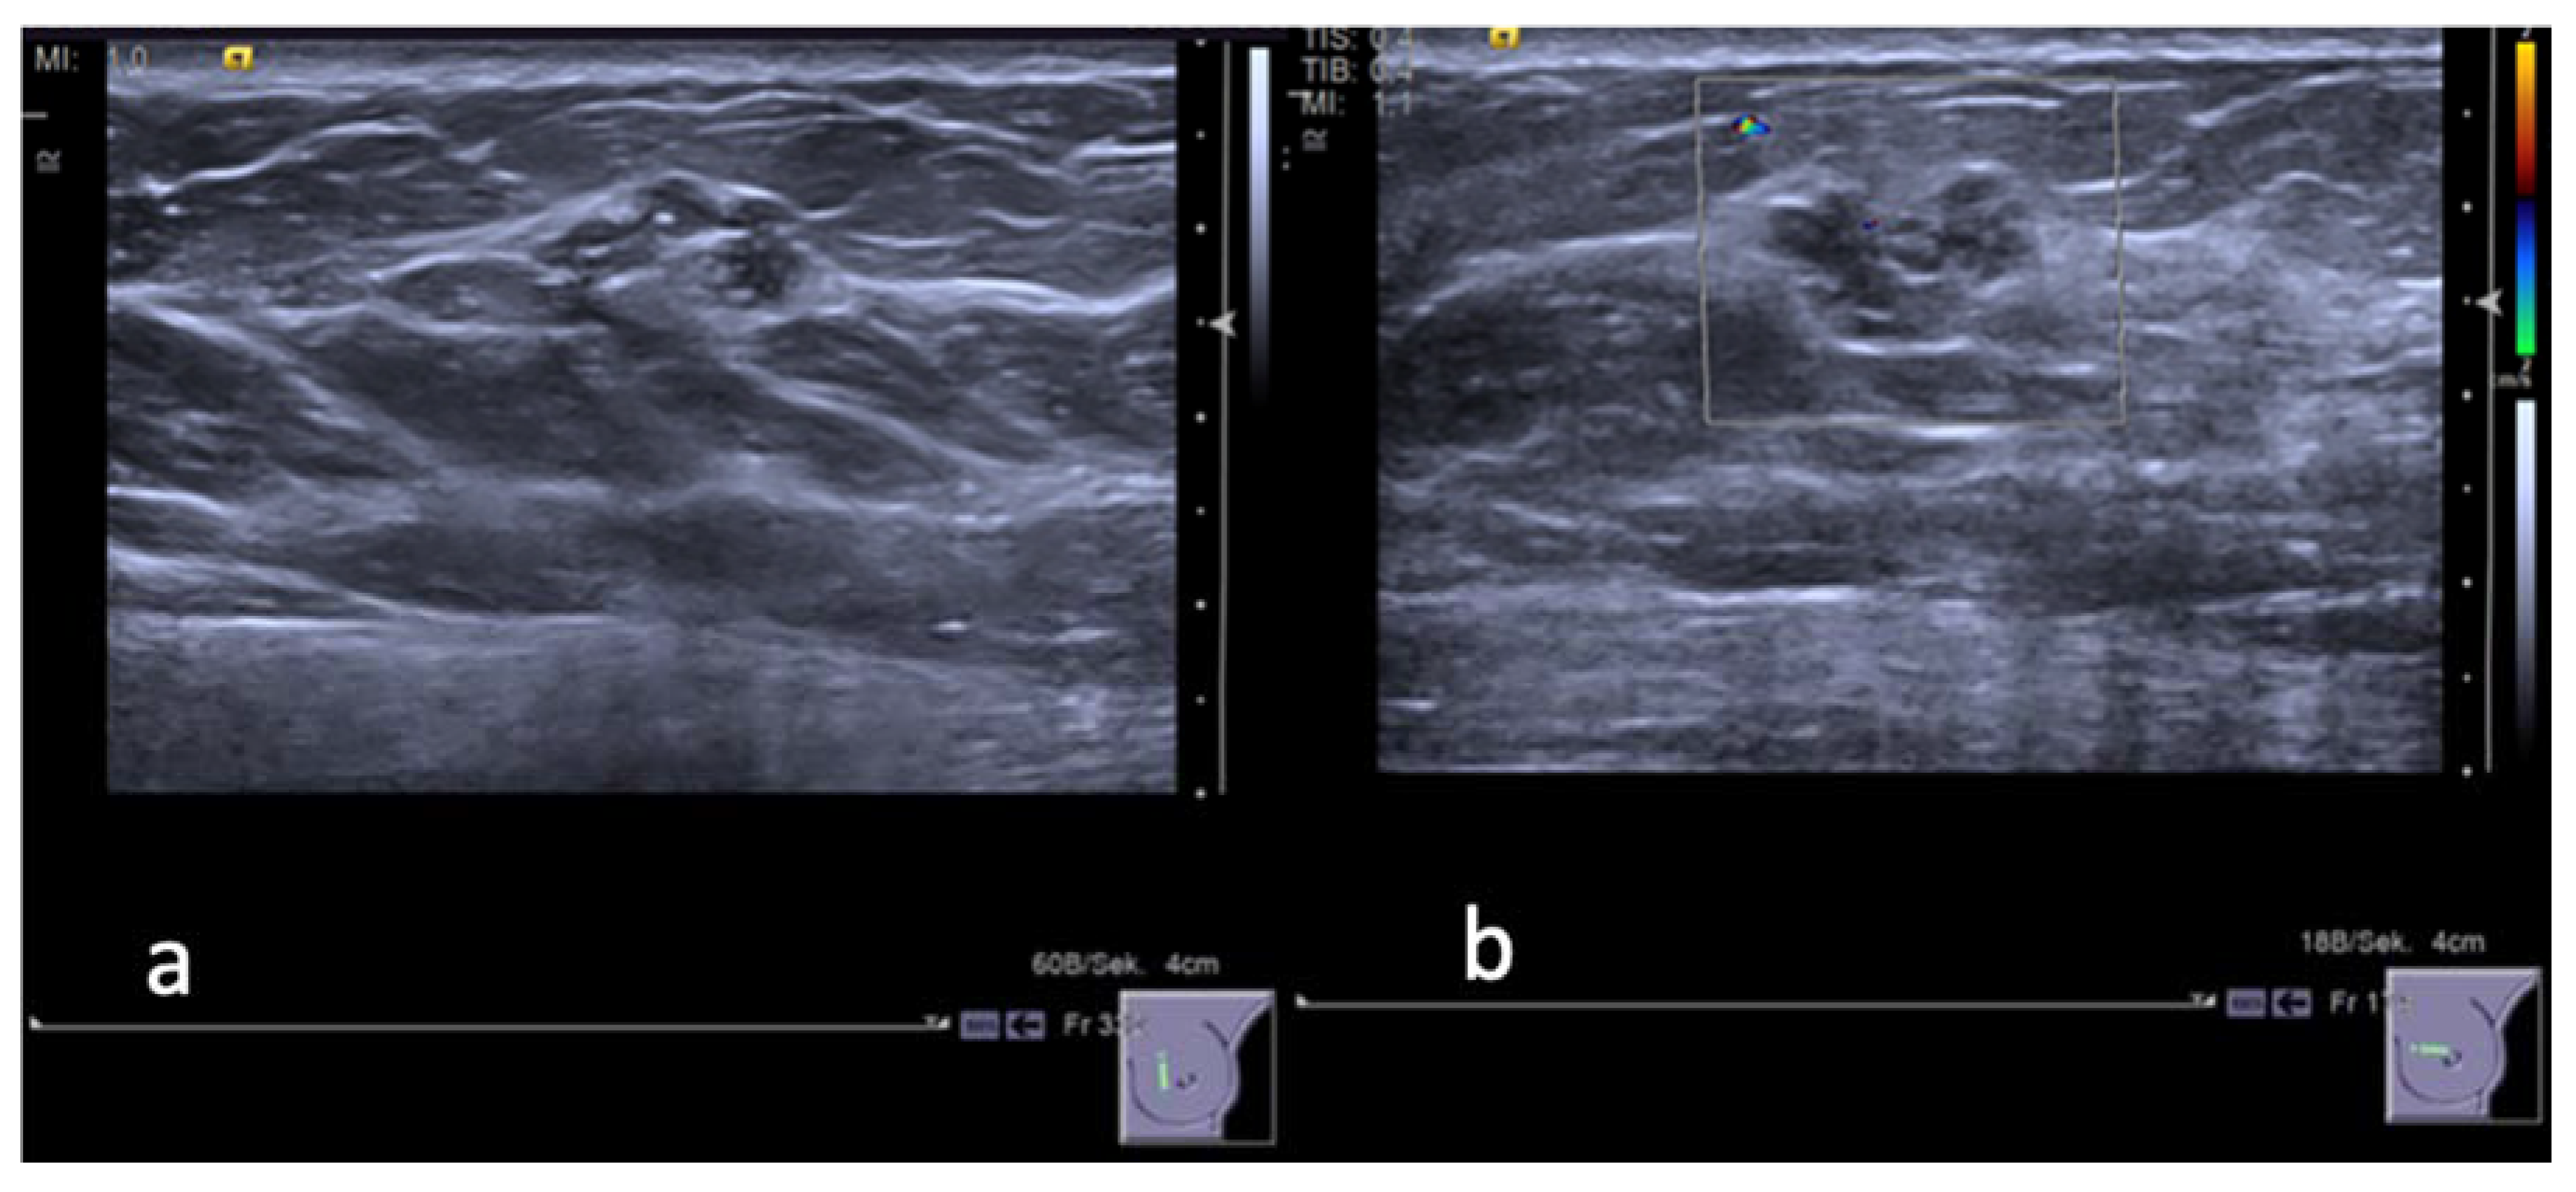

2.2. Biopsy Technique